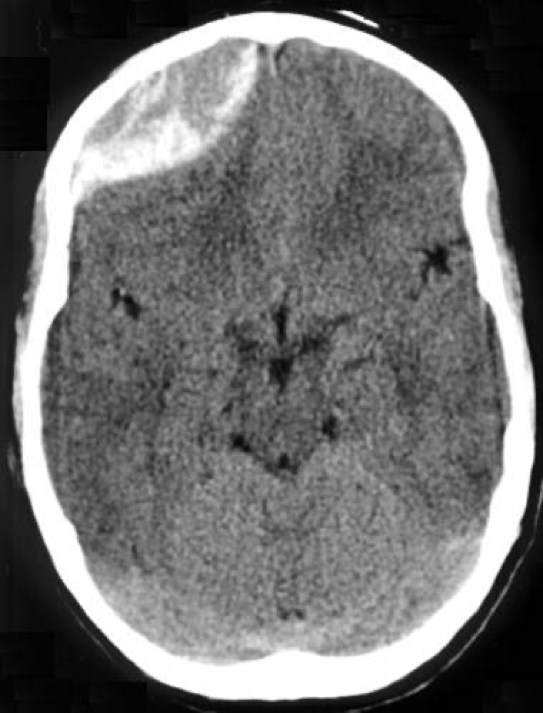

Investigations

- CT Head:

- Acute: Crescent-shaped density

- Chronic: Hypodense, follows brain contour

- Midline shift may be present